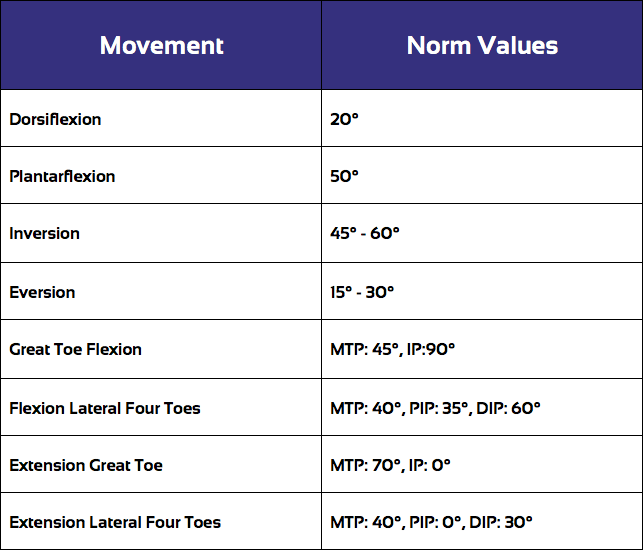

Det er bedst at starte med en vurdering af den aktive bevægelsesradius:

Standardværdierne for bevægelsesområdet i forskellige retninger er som følger:

AROM-vurderingen efterfølges typisk af en vurdering af passivt bevægelsesudslag (PROM), som du kan se ved at klikke på følgende video:

Under PROM-vurderingen er det vigtigt at sammenligne bevægelsesområdet og slutfornemmelsen af den påvirkede ankel med den upåvirkede side.